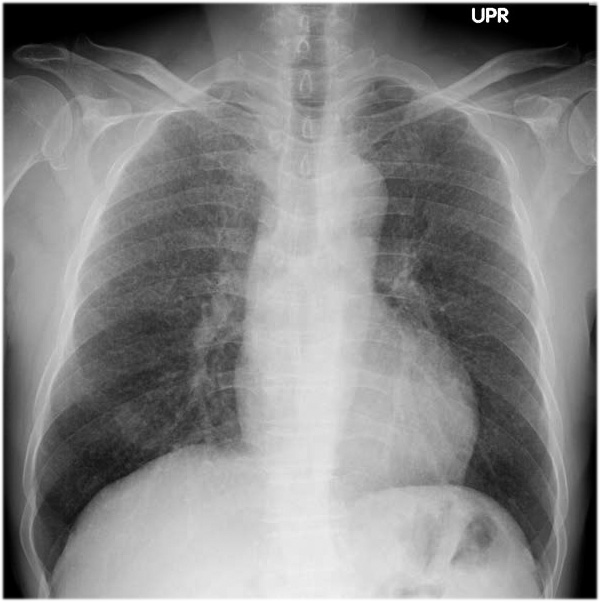

Miliary pattern

Diffuse micronodules typically 2-3 mm (TB)